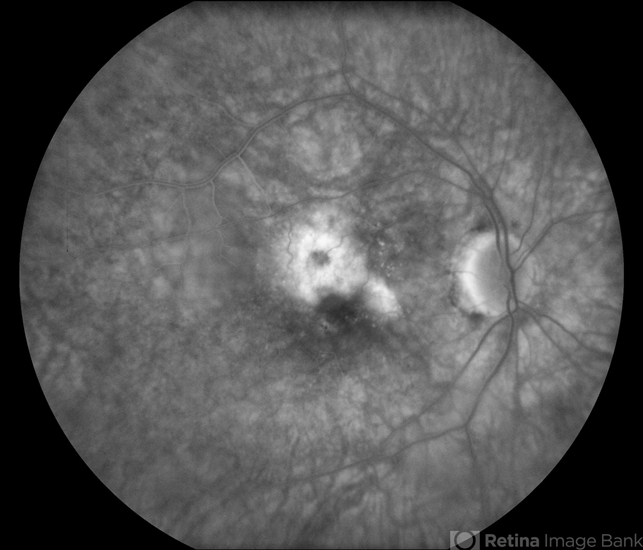

- Macular Degeneration (AMD)

- choroidal neovascularization (CNV)

- Fluorescein angiography shows early staining which represents classic CNV.